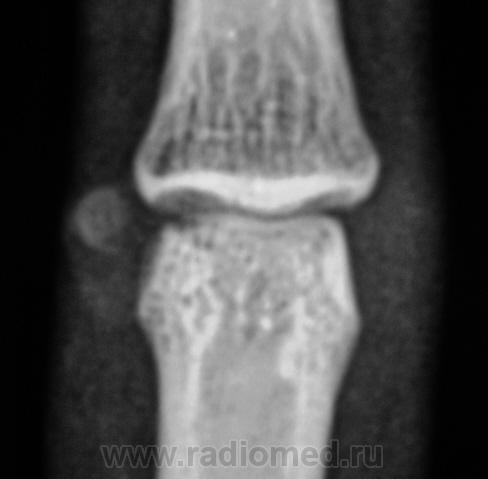

Пациент направлен на рентгенографию пальца.

Думаю это по аналогии с болезнью Кёнига - виден дефект суставной поверхности и в суставе - хондроматозное тело. Редкое наблюдение!

Вы правы, сегодня, это хондроматозное тело и вылущили.